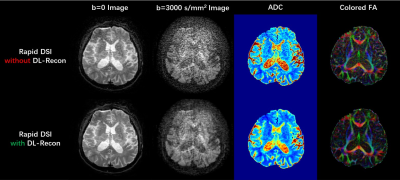

As shown in Figure 1, the rapid DSI sequence can drastically shorten the scan time by using a higher hyperband acceleration factor and fewer diffusion encoding directions, at the cost of extremely low SNR of diffusion images and quantitative metric maps under conventional reconstruction. The application of DL-recon significantly improved the SNR and quality of all images and maps. The tractography results for complex white matter fiber structures (Figure 2) manifest that the rapid DSI lost the ability to resolve crossing fibers, which can be restored by implementing DL-recon. Figure 3 demonstrates that the rapid DSI with DL-recon can provide abundant quantitative diffusion metrics with similar quantitative accuracy to conventional DSI only with a fraction of the data set and hence the scan time. Moreover, it is worth noting that the obvious Gibbs-ringing artifacts, which may be due to the relatively low in-plane resolution of the DSI scan and will theoretically contaminate both conventional and rapid DSI quantitative maps, can be effectively eliminated by DL-recon. From this perspective, rapid DSI with DL-recon can even provide higher quality quantitative results than conventional DSI.

Fig. 1. Images (and corresponding quantitative metric maps) acquired using rapid DSI sequence in 8 min, and reconstructed using conventional (upper row) and DL-based method (lower row). ADC: apparent diffusion coefficient; FA: fractional anisotropy.